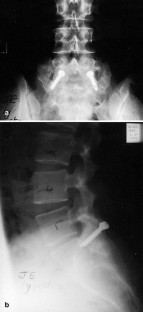

Fig. 1. a